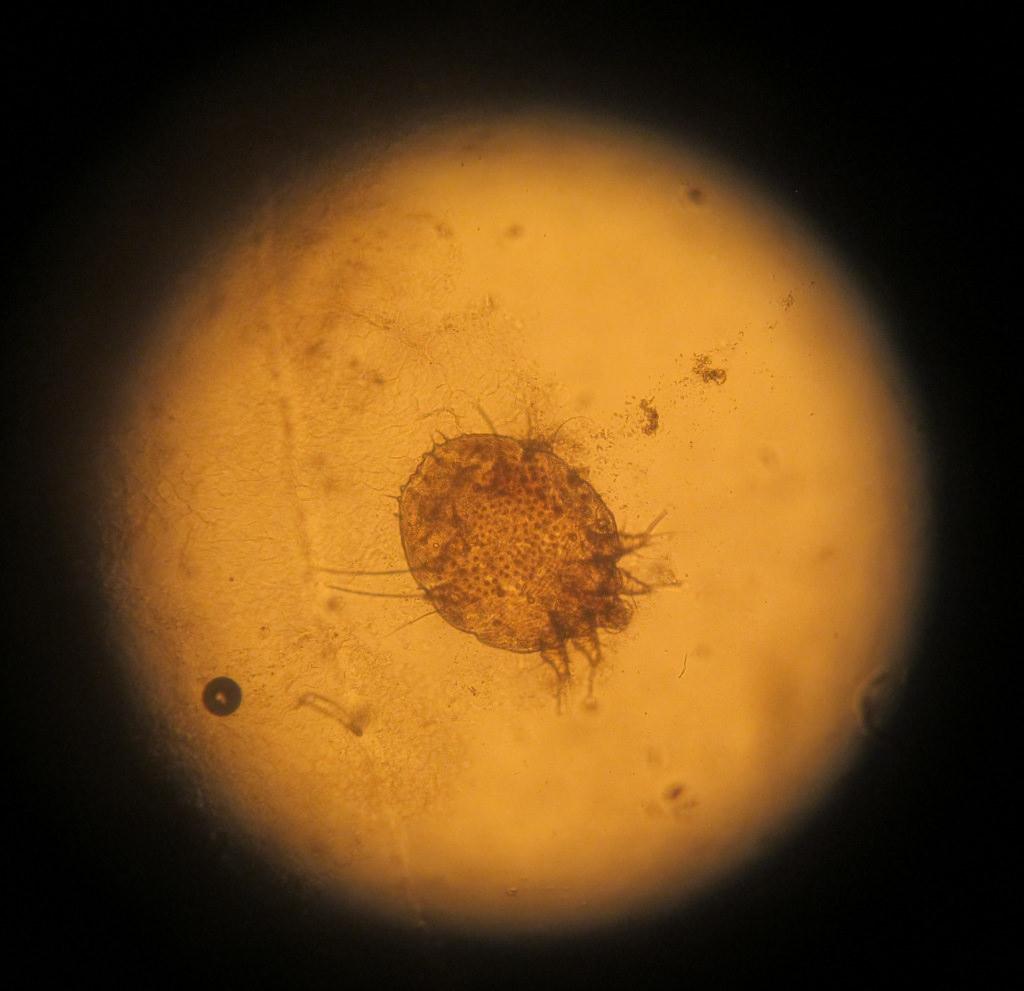

Причина появления поражений – паразит Sarcoptes scabiei. Переносить его может любое живое существо, которое подверглось заражению. И чем больше поражений на теле больного, тем выше риск, что он может кого-то заразить.

как выглядит чесоточный клещ

Заражение осуществляют самки и личинки. Самка обитает в коже. В дневное время она неактивна, но вечером она активно прогрызает ходы, размножается, питается и выделяет продукты переработки. Следовательно, самый большой риск заразиться появляется именно в вечернее-ночное время, когда клещ проявляет большую активность.

Клеща можно обнаружить с помощью молочной кислоты. Одну каплю (40%) нужно нанести на любое поражение и подождать 5 минут. После разрыхленную кожу можно соскоблить острой ложкой, пока не появится капиллярное кровотечение. Полученный эпидермис нужно нанести на предметное стекло и посмотреть на него под микроскопом. Метод позволит определить большинство паразитов и продуктов их активности.